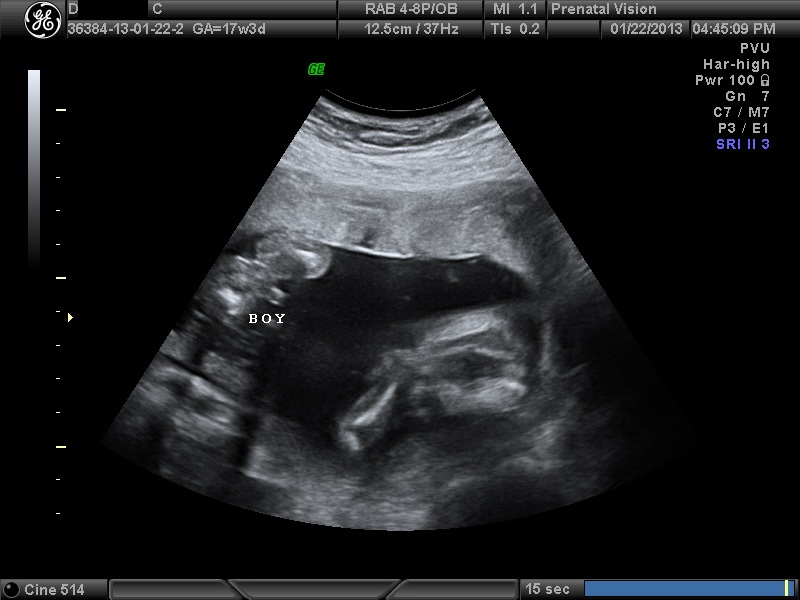

IMAGES_16 January 22, 2013 by Courtney Leave a comment ← Previous Image Next Image → 17w3d – Our second BOY! Like Loading...